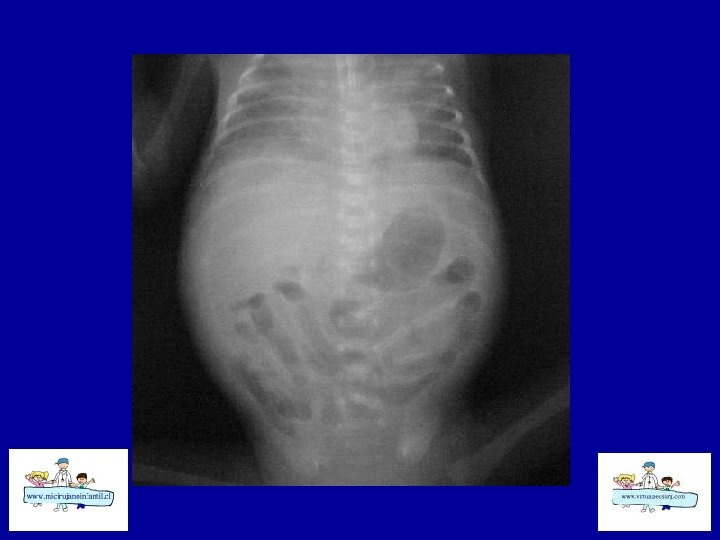

ECN-RADIOLOGÍA SIMPLE • • Distensión de asas Pneumatosis intestinal Asa fija (centinela) Gas Porta Edema de pared Ascitis Aire libre

ECN- CLASIFICACION (Bell) Etapa I: sospecha a CEG, sepsis inicial, Rx. distensión de asas moderada Etapa II: confirmada Ileo, sepsis más intensa , Rx: Ileo – pneumatosis b Hematoquezia Celulitis de pared, masa, grave, Rx: ascitis, gas porta Etapa III: grave Muy grave, CID, peritonitis Rx: ascitis Rx : pneumope ritoneo